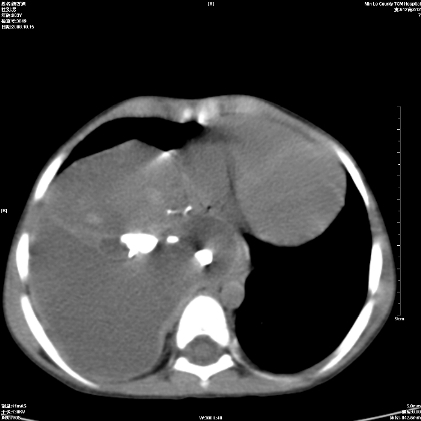

标题: PED1609:男性,3岁。彩超示肝Ca. [打印本页]

标题: PED1609:男性,3岁。彩超示肝Ca.

考虑后纵隔恶性畸胎瘤伴肝内多发转移可能性大,右侧肾上腺转移不除外.

3岁;肝低密度灶;有钙化;有转移灶;考虑肝母细胞瘤;查afp

考虑神经母细胞瘤并肝转移

考虑:1、右侧后下纵隔畸胎瘤。

2、肝脏多发血管内皮细胞瘤。

建议:增强确诊。